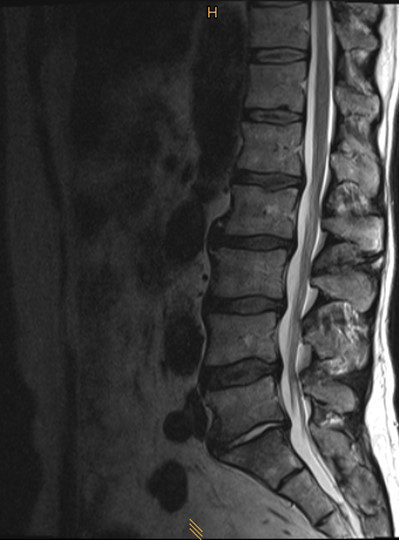

A 52-year-old male patient presented with low back pain and S1 radicular pain on the left side for 3 weeks. The laboratory tests of the blood showed enhanced inflammation signs. The MRI showed an infection of the L5/S1 disc (Fig 1). Indications for minimally invasive spondylodesis with intervertebral cage (Figs 2-6).